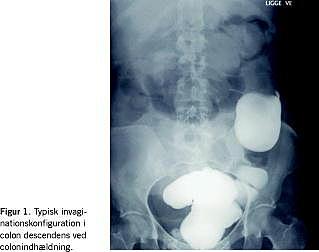

En 47-årig kvinde blev indlagt akut på medicinsk afdeling på grund af ukarakteristiske mavesmerter. Ved en objektiv undersøgelse, biokemi, gastroskopi og røntgenoversigt over abdomen blev der fundet normale forhold. Ca. en måned senere blev patienten henvist akut af en vagtlæge til kirurgisk vurdering på grund af akut opståede smerter under umbilicus, lidt kvalme og vekslende afføring gennem et par dage. Objektivt fandtes der intet abnormt, en urinstik viste 3+ for leukocytter og 4+ for blod, hvilket blev tolket som cystit og behandlet med sulfamethizol. Tre dage senere blev hun indlagt akut på en kirurgisk afdeling grundet tiltagende mavesmerter. Ved en objektiv undersøgelse blev der fundet en 15 cm stor, øm udfyldning over nedre abdomen og klingende tarmlyde. En røntgenoversigt over abdomen viste subileus, fri tyndtarmspassage, men langsom kontrastpassage, der var ingen inflammatoriske forandringer og tyndtarmen var displaceret mod højre af en patologisk udfyldning i venstre fossa iliaca. Ved en UL-skanning af abdomen påvistes en hypoekkotisk masse med en koncentrisk ring (double ring sign ). En røntgenundersøgelse af colon med bariumkontrast viste venstresidig kolokolisk invagination (Figur 1 ). Der blev foretaget subakut laparotomi. Peroperativt blev der fundet kolokolisk invagination med invaginat hele vejen over til colon descendens. Man valgte at foretage højresidig hemikolektomi. Det opklippede præparat viste en caecumtumor, alternativt svære inflammatoriske forandringer ved appendix. Den øvrige del af colon og tyndtarmen var uden patologi, og der var ingen matastasesuspekte forandringer i hepar. Histologisvar viste adenocarcinoma i caecum T3N0M0 (Dukes type B). Ti dage efter operationen blev patienten udskrevet uden efterbehandling. En efterfølgende kontrolkoloskopi viste normale forhold.